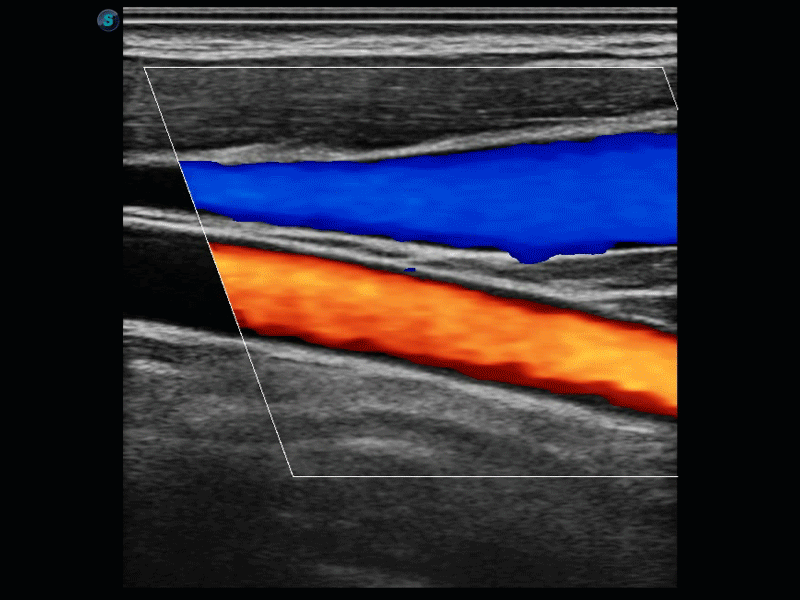

SR Flow高分辨率血流成像

高分辨率血流成像技术提高了对低速血流信号的检测能力。在提高空间分辨率的同时,也克服了血流外溢现象,为用户提供更加真实的血流动力学信息。